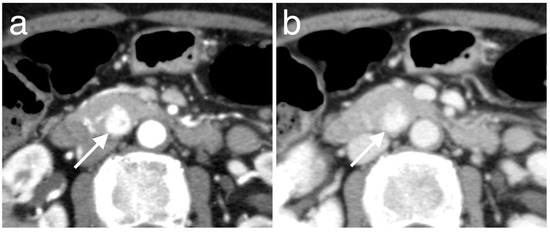

3.3. Enhancement Patterns of Pan-NENs Related to Low or High PAX6 Expression

| Hyperenhancement | 4 | 32 | 0.64 | 0.009 |

| Iso- or hypoenhancement b | 7 (3, 4) | 8 (6, 2) | ||

| Hyperenhancement | 3 | 33 | 0.76 | 0.001 |

| Iso- or hypoenhancement b | 8 (6, 2) | 7 (6, 1) | ||